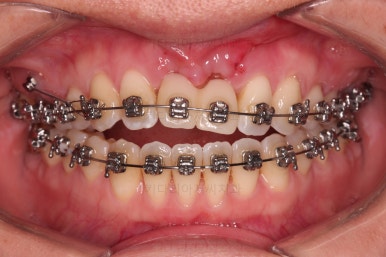

개방교합도 많이 다물어졌고, 2급 부정교합도 매우 많이 개선되었네요.

임플란트 가능 시점이 점점 다가오는데요.

임플란트를 한 번 하게되면 많은 치아 움직임은 없어야 되기 때문에, 앞니의 높이, 입매, 교합 등등 모든 점에서 평가가 진행됩니다.

얼굴모습에서의 평가도 이루어지고요.

잇몸뼈의 상태에 비해 매우 양호하게 임플란트가 완성되었고요.

개방교합, 2급 부정교합 등 모든 면에서 개선이 잘 되었습니다.